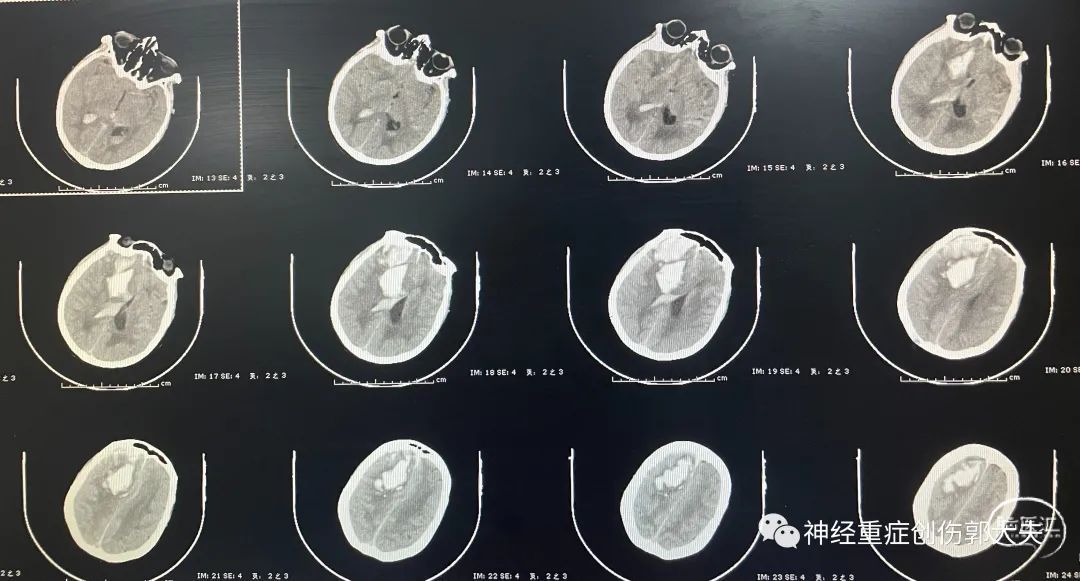

患者男性,52岁,主因“意识障碍8小时”入院,神志中昏迷,GCS5分,既往高血压病史,头颅CT显示左侧基底节区脑出血破入脑室。

急诊行右侧脑室外引流+左额颞顶开颅血肿清除+去骨瓣减压术,术后复查移动CT显示引流管位于侧脑室内,血肿清除满意。